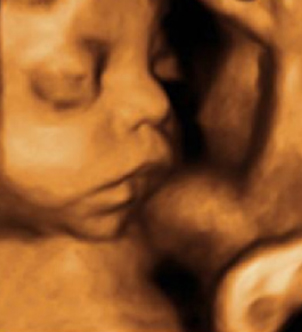

Salud fetal. En el ultrasonido es posible constatar la salud del bebé al tomar sus medidas, observar el flujo sanguíneo y simplemente al verlo mover y actuar. Un bebé sano se estira y flexiona, mueve sus brazos y piernas, abre y cierra las manos, agita los dedos de la mano y del pie y mueve sus labios y lengua. Respira el líquido amniótico y esto le ayuda a madurar sus pulmones. Podrás tener una idea de cómo será tu bebé simplemente con la foto que tomarán de su carita.